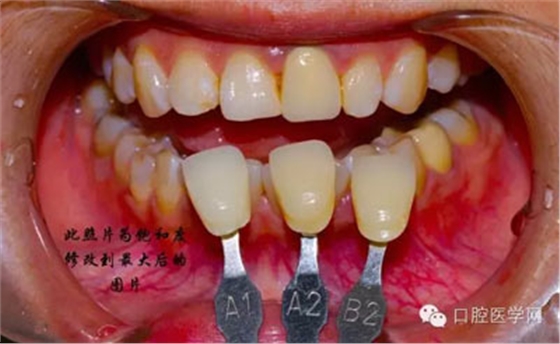

將比色照的飽和度調(diào)到最高有助于牙齒道飽和度選擇

7、術(shù)后照飽和度調(diào)到最低與最高,觀察牙齒修復(fù)后的明度及飽和度